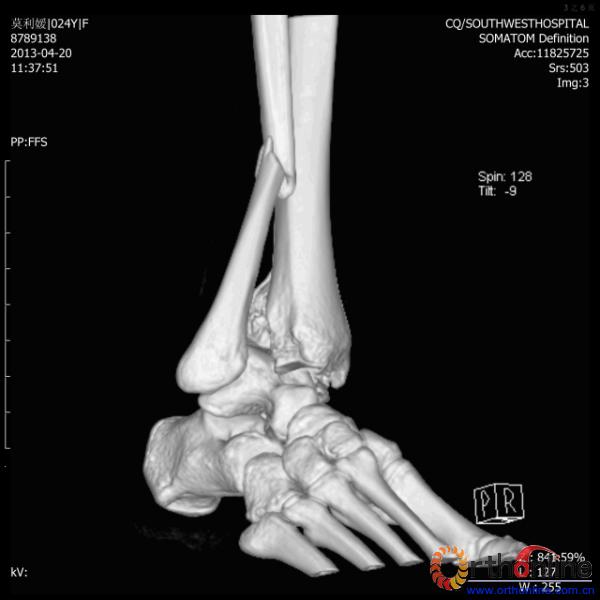

2013年4月20日 8:02分四川雅安芦山县发生7.0级地震后,重庆市有震感,24岁的莫老师在赶往上班的途中突遇此事,导致右踝关节畸形,不能站立和行走。

伤员和家属迅速赶到西南医院,10点关节外科段小军副教授查看伤员后急诊收入院,拍摄X片和急诊行三维CT重建检查,提示踝关节创伤严重,出现三踝骨折伴胫距关节脱位,需要急诊手术治疗。随后段教授与正在四川成都参加“汶川地震5周年灾害医学救治研讨会”的杨柳主任联系,进一步完善救治方案。地震当晚,段教授为该伤员进行急诊手术,手术顺利对复杂骨折进行了解剖复位,有效的钢板螺钉固定。术后伤员的疼痛明显缓解,复查X片,踝关节结构恢复满意。

患者术前CT(二)